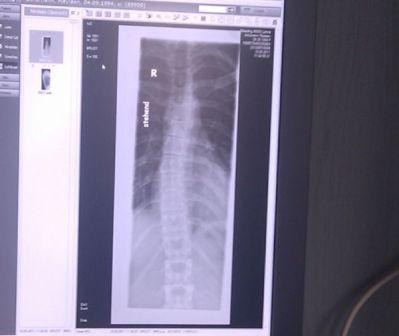

Hier habe ich ein Bild gefunden, was wir mal in der Praxis gemacht haben als ich den Arzt gewechselt habe und geröntgt wurde. Vielleicht könnt Ihr da auch schon einen Eindruck gewinnen?

- ich hätte es gern größer geschickt, ging aber nicht...

- IMAG0226ab.jpg (20.99 KiB) 9869 mal betrachtet

so ein schräg aufgenommenes Bild kann täuschen; aber sieht jetzt zumindest nicht so dramatisch aus ... Skoliose ja, behandlungsbedürftig auch, aber über 25° wird die kaum sein.

Dürfte mit zielgerichteter Gymnastik in den Griff zu kriegen sein.

Meine Röntgenbilder sind alle bei den Ärzten und in der Klinik, das Foto, welches ich hier eingestellt habe, habe ich mit meinem Handy gemacht, als wir beim Arzt waren, deswegen ist die Aufnahme auch so schief - ich dachte nur, dass Ihr so wenigstens einen kleinen Eindruck habt. Am Montag werde ich fragen, ob ich die Bilder, die bei ihm vorliegen bekommen kann und in der Klinik werde ich mich auch mit der Bitte melden - ich denke ich brauche sie sowieso hier Zuhause für alles was ich jetzt weiter in Angriff nehme. Gestern habe ich schon angefangen sämtliche Praxen für Physiotherapie und Krankengymnastik anzurufen, wegen der Schroth-Therapie, aber Freitag nachmittag habe ich kaum noch jemanden erreicht. Montag geht es weiter und vielleicht kann ich meinen Orthopäden auch drauf anspitzen - vielleicht hat er auch ein paar Adressen. Den Rehasport habe ich ihm auch aus der Nase gezogen und bewilligt bekommen...